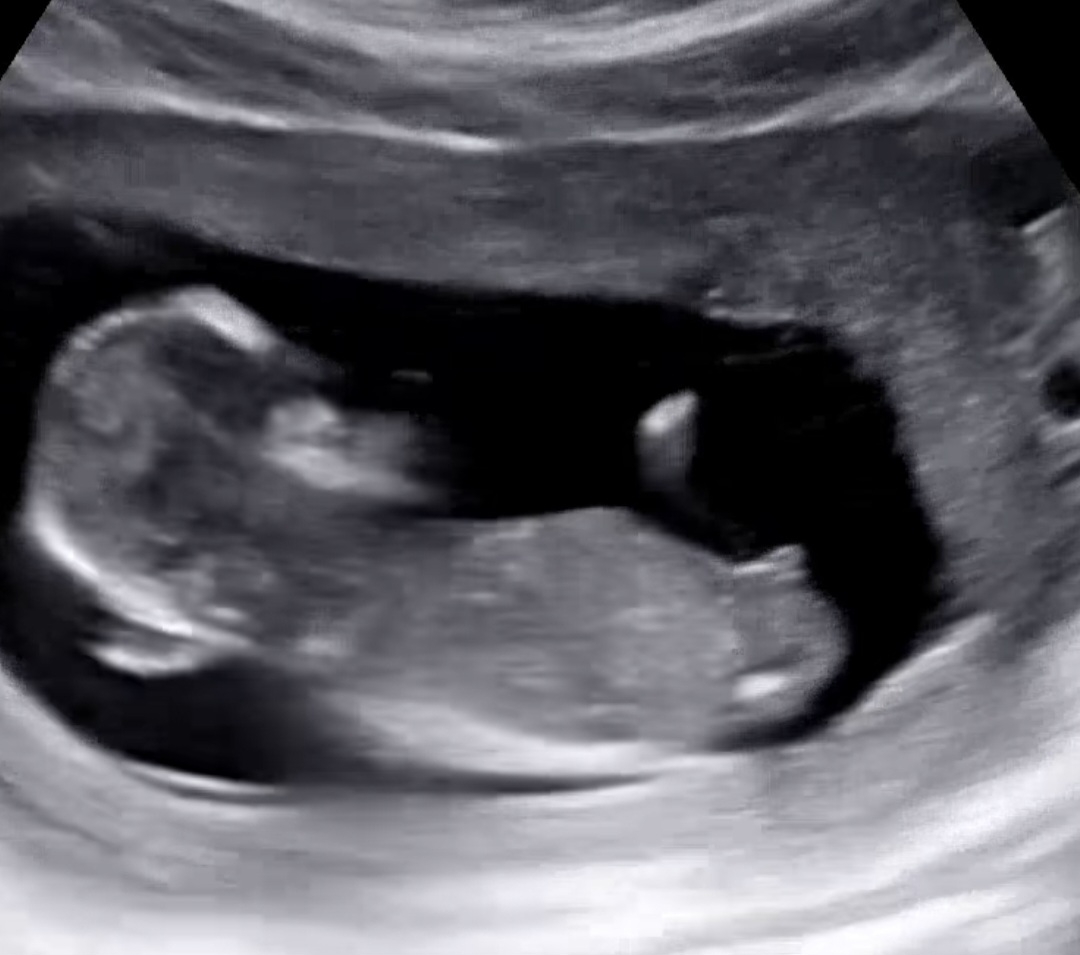

성별 남아 여아 부탁드릴께요♥

초음파 사진을 올리면 AI가 무료로 예측해줘요